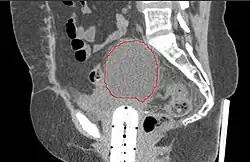

A CT scan of post-operative lymphocele

A lymphocele is a collection of lymphatic fluid within the body not bordered by epithelial lining.[1] It is usually a surgical complication seen after extensive pelvic surgery (such as cancer surgery) and is most commonly found in the retroperitoneal space. Spontaneous development is rare.[2]

Many lymphoceles are asymptomatic. Larger lymphoceles may cause symptoms related to compression of adjacent structures leading to lower abdominal pain, abdominal fullness, constipation, urinary frequency, and edema of the genitals and/or legs. Serious sequelae could develop and include infection of the lymphocele, obstruction and infection of the urinary tract, intestinal obstruction, venous thrombosis, pulmonary embolism, chylous ascites and lymphatic fistula formation.[1] On clinical examination the skin may be reddened and swollen and a mass felt. Ultrasonography or CT scan will help to establish a diagnosis. Other fluid collections to be considered in the differential diagnosis are urinoma, seroma, hematoma, as well as collections of pus. Also, when lower limb edema is present, venous thrombosis needs to be considered.[3]